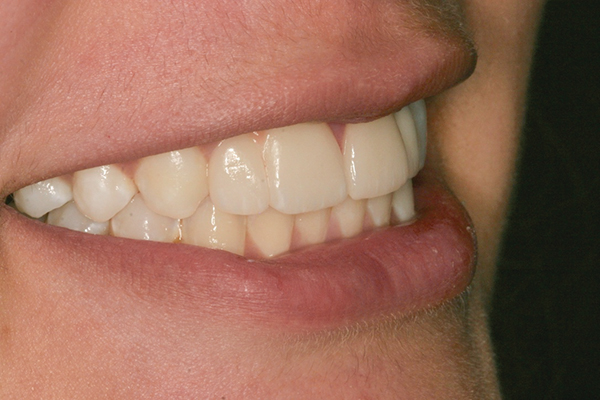

Fig 1 and Fig 2. Pretreatment photographs. Patient at 9 years of age on presentation.

A 9-year-old girl, referred to a prosthodontic office by her pediatric dentist, presented with her mother’s chief complaint: “The kids are teasing her about her big front tooth.” Findings from radiographic and clinical examinations revealed fused maxillary central-peg lateral incisors, teeth Nos. 7 and 8, and a congenitally missing lateral incisor, tooth No. 10 (Figure 1 through Figure 3). An implant was selected as the ideal treatment to replace tooth No. 10 when somatic growth was complete. A diagnostic wax-up was fabricated to determine if the fused tooth could be made to resemble two teeth, using pink composite to give the illusion of an interproximal papilla. The patient was referred for an orthodontic consultation to plan for closure of the diastema between teeth Nos. 8 and 9 and achievement of proper alignment for implant No. 10. The patient was also referred to a periodontist for pretreatment assessment of the tooth No. 10 site. An endodontist was consulted should exposure of the large pulp occur during tooth preparation.